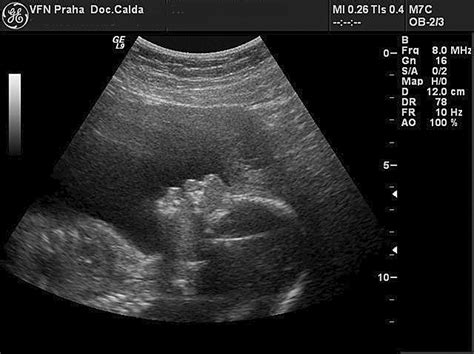

Nízko Uložená Placenta (Placenta Praevia)

Nízko uložená placenta, známa aj ako placenta praevia, je stav, kedy placenta v maternici rastie príliš nízko a môže čiastočne zasahovať alebo úplne blokovať vnútornú bránku, teda otvor do pošvy. Placenta praevia sa väčšinou diagnostikuje v druhej polovici tehotenstva. Tento stav sa vyskytuje len u 0,5 % žien v čase pôrodu.

Diagnostika a Monitorovanie

Rodička s diagnózou placenta praevia je pravidelne monitorovaná lekárom. Ak má lekár pocit, že placenta rastie príliš blízko krčka maternice, nevykonáva vaginálne vyšetrenie, nakoľko by mohlo spôsobiť krvácanie. Plod sa pri tejto diagnóze väčšinou nachádza v priečnej alebo šikmej polohe.

Riziká Placenty Praevia

Pri vyšších stupňoch placenty praevia je dokonca vyššie riziko úmrtia matky alebo dieťaťa pri pôrode. O spôsobe pôrodu rozhoduje lekár. Ak máte prvý alebo druhý stupeň placenty praevia, teda placenta neprekrýva vnútornú bránu, je možné, že budete rodiť vaginálne. Pri treťom a štvrtom stupni placenta praevia takmer všetky pacientky rodia cisárskym rezom. Vaginálny pôrod by v tomto prípade prinášal príliš veľké riziká, vrátane vykrvácania rodičky a úmrtia plodu.